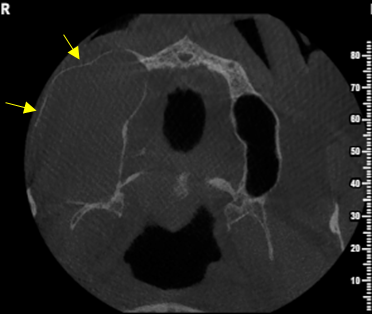

Περίπτωση ιδιαίτερα εκτεταμένης υπολειμματικής κύστης που καταλαμβάνει σχεδόν όλο το δεξιό ημιμόριο της άνω γνάθου εμπλέκοντας και το δεξιό ιγμόρειο άντρο σε γυναίκα ασθενή ηλικίας 75 ετών.

Η κύστη καταλαμβάνει πλήρως τη φατνιακή ακρολοφία στην οπίσθια δεξιά περιοχή της γνάθου και έχει προκαλέσει ιδιαίτερα εκτεταμένη υπέγερση του εδάφους του ιγμορείου άντρου προβάλλοντας εντός αυτού και καταλαμβάνοντας μεγάλο τμήμα της αεροφόρου του κοιλότητας.

Παρατηρείται επίσης ιδιαίτερα εκτεταμένη έκπτυξη και λέπτυνση του πλαγίου τοιχώματος του ιγμορείου άντρου, καθώς και των συμπαγών πετάλων της φατνιακής ακρολοφίας.

Σε αυτές τις περιπτώσεις η Υπολογιστική Τομογραφία Κωνικής Δέσμης (CBCT) μπορεί να βοηθήσει καταλυτικά στη διαφοροδιάγνωση αυτών των βλαβών αλλά και να αποκαλύψει με λεπτομέρεια την έκταση και τα όρια της βλάβης.